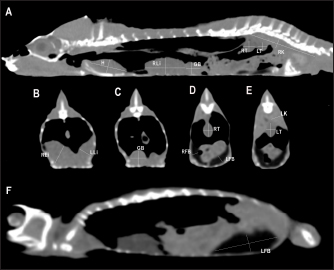

Fig. 5. Sagittal precontrast CT image displayed in soft tissue window (A) and selected corresponding transverse images represented as green line section, displayed in soft tissue (B, D–G) and lung window (C) at the level of the lungs, liver (D), gastrointestinal tract (E), fat bodies (F), and kidneys/urinary bladder (G) in a panther chameleon (F. pardalis). The right of the patient is on the left of the image. RLu, right lung; LLu, left lung; Es, esophagus; RLi, right liver lobe; LLi, left liver lobe; St, stomach; I, intestine; GB, gallbladder; RK, right kidney; LK, left kidney; RT, right testicle; LT, left testicle; Co, colon; RFB, right fat body; LFB, left fat body; U, urinary bladder with intraluminal content (urate salts) in the lumen visualized as multiple irregular mineral attenuating structures.

Fig. 6. Sagittal right paramedian precontrast CT image displayed in soft tissue window (A) and selected corresponding transverse images represented as green line section, displayed in soft tissue window at the level of the gallbladder (B), fat bodies (C), and kidneys/urinary bladder (D) in a veiled chameleon (C. calyptratus). H, heart; RLu, right lung; LLu, left lung; Es, esophagus; RLi, right liver lobe; LLi, left liver lobe; GB, gallbladder; RK, right kidney; LK, left kidney; RT, right testicle; LT, left testicle; I, intestine; RFB, right fat body; LFB, left fat body; U, urinary bladder; LF, left femur; RF, right femur; PB, pelvic bone.

Lungs

Due to the air attenuation of both lung fields and air sacs, it was not possible to delineate well-defined limits between them in a soft tissue window, where they were visualized together as a large air-attenuating structure (Figs. 5 and 6). Air sacs occupy more than two-thirds of the dorsal coelom, and lung volume is wide variable depending on their degree of expansion. Because of this, no measurements for lung size were taken. With the lung window, the lung parenchyma in the prehilar portion of the lungs appeared as a thin, faintly outlined, homogeneous, and hypoattenuating area surrounding an air-filled cavity (Fig. 5); in the posthilar portion of the lungs, the parenchyma was barely visible. A transverse septum could be observed as a thin, hyperattenuating structure along the lungs. The caudal portion of the gas-attenuating structure corresponded to the air sacs (Fig. 6).